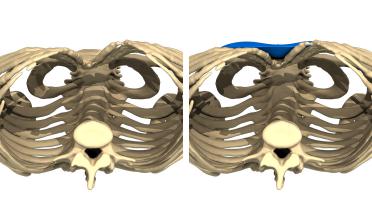

La tecnica di impianto su misura è una tecnica chirurgica minore che consiste nel riempire la concavità creata dal Pectus con un impianto personalizzato. Si tratta di un intervento rapido, a basso rischio, con un risultato immediato e una breve convalescenza.

In questa pagina, troverà i risultati di questa operazione a seconda del tipo di Pectus : mediale, asimmetrico, più o meno profondo o lungo.

Tipo 2 : Ampio, poco profondo e simmetrico,